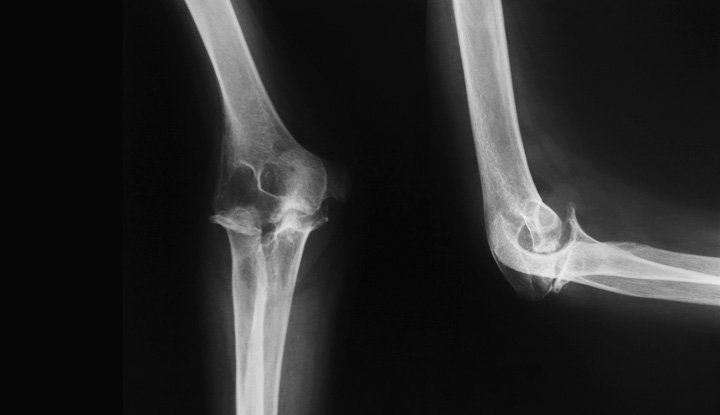

Understanding Elbow Anatomy

The elbow is a complex joint consisting of three bones: the humerus, radius, and ulna. The movements that can be performed by this joint are flexion, extension, and forearm rotation. The joint is encapsulated by muscles, tendons, ligaments, and bursae, which enable it to move smoothly. Pain could be a result of inflammation, degeneration, or trauma to any of the above structures. Understanding the underlying cause is key to effective elbow pain treatment in Bangalore.

Diagnosis of Elbow Pain